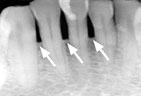

| Advanced Periodontitis |